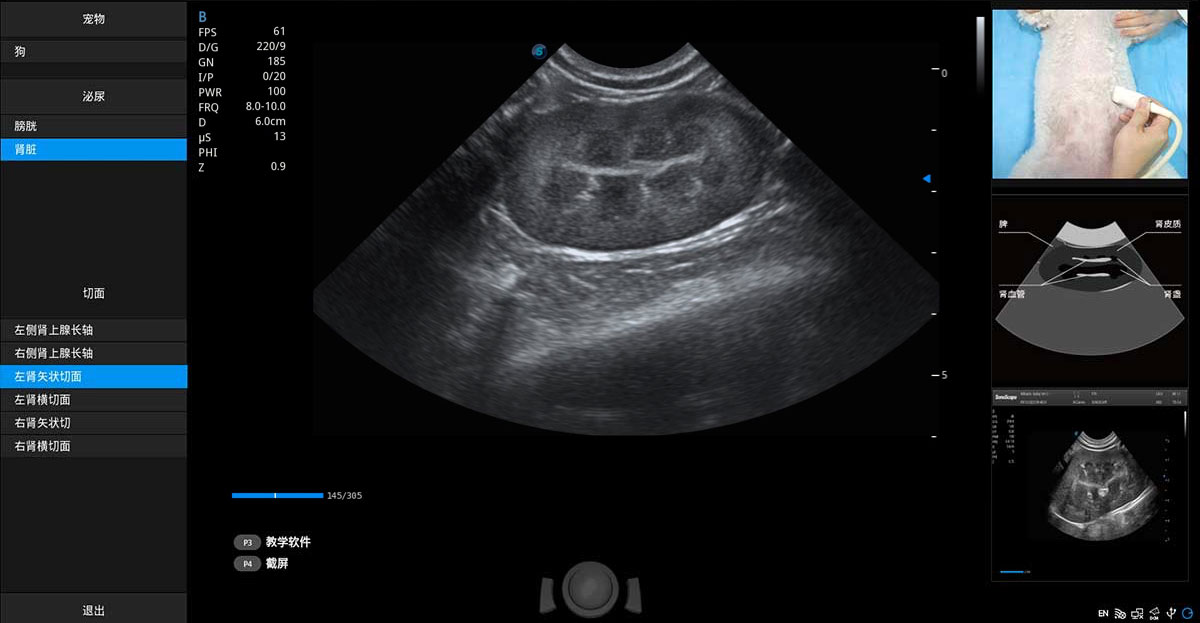

提供解剖示意圖、標(biāo)準(zhǔn)超聲圖像、掃查手法圖和操作者實(shí)時(shí)檢查圖像,指導(dǎo)操作者進(jìn)行標(biāo)準(zhǔn)切面的正確掃查。

ProPet 70專為動(dòng)物醫(yī)生設(shè)計(jì),對(duì)不同的動(dòng)物體型和生理結(jié)構(gòu)作出了針對(duì)性的優(yōu)化。通過(guò)動(dòng)物影像專用軟件,可滿足個(gè)性化的應(yīng)用需求,幫助動(dòng)物醫(yī)生獲得更精確的診斷數(shù)據(jù)。